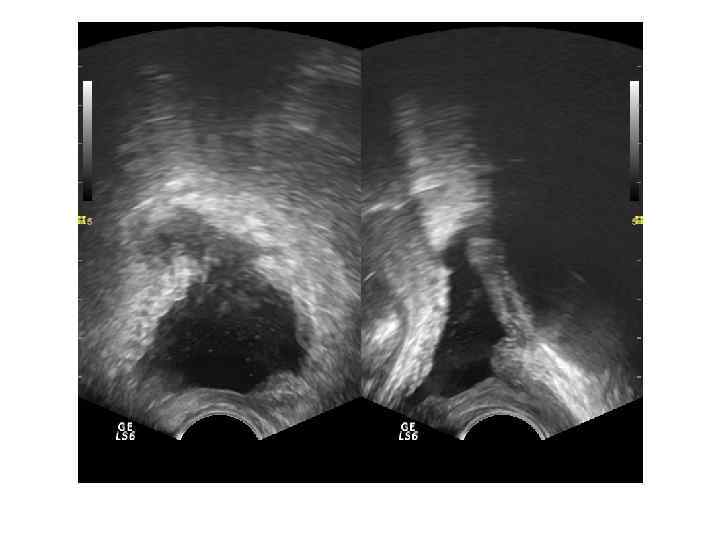

Абсцесс предстательной железы имеет достаточно характерную ультразвуковую картину: одно или несколько объемных образований в паренхиме простаты чаще округлой или овоидной формы с толстой слоистой стенкой и неоднородным жидкостным содержимым, с усилением сосудистого рисунка по периферии. ТРУЗИ болезненно!!